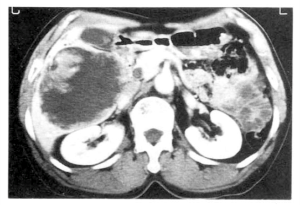

A rara e congênita doença hepática policística está associada à doença policística dos rins e de outros órgãos. Produz hepatomegalia nodular progressiva (por vezes, maciça) em adultos. No entanto, a função hepatocelular é notavelmente bem preservada e a hipertensão portal se desenvolve raramente. Ocasionalmente, cistos muito grandes causam dor ou sintomas decorrentes da compressão de outros órgãos. Nesses casos, pode-se considerar intervenção como marsupialização ou drenagem de cistos; contudo, os cistos costumam recorrer. Portanto, raramente, sintomas graves ou questões de qualidade de vida justificam a consideração de transplante de fígado.